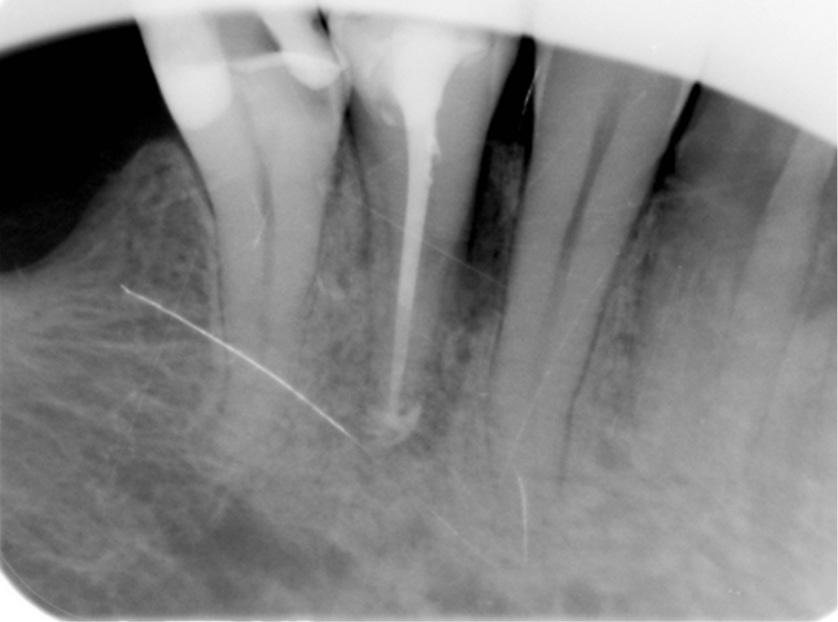

Wprowadzenie. Sukces leczenia kanałowego zależy od prawidłowo wykonanych procedur endodontycznych przeprowadzonych podczas mechaniczno-chemicznego opracowania i wypełnienia systemu kanałowego. Przed przystąpieniem do zabiegu należy zawsze zapoznać się ze zmiennością morfologii systemów kanałowych w leczonej grupie zębów. Cel pracy. W pracy przedstawiono postępowanie kliniczne pozwalające na przeprowadzenie skutecznego leczenia kanałowego zębów przedtrzonowych dolnych. Podsumowanie. Leczenie endodontyczne zębów przedtrzonowych żuchwy często jest zabiegiem trudnym, wymagającym dokładnej znajomości anatomii systemu kanałowego, umiejętności i zdolności manualnych lekarza oraz odpowiedniego sprzętu i urządzeń powiększających.

Introduction. The success of root canal treatment depends on properly conducted endodontic procedures performed during chemo-mechanical preparation and obturation of the canal system. Anatomical variations of root canal systems in the treated group of teeth should be always considered before initiating endodontic procedure. Aim. The article presents clinical procedure that allows effective root canal treatment of mandibular premolars. Summary. Endodontic treatment of mandibular premolars is often a difficult procedure, requiring a thorough knowledge of the anatomy of the root canal system, skills and [...]